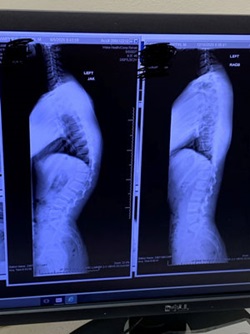

X-ray of Patient Griffin's BackWhen Griffin Lamphier, 14-year-old Winston-Salem Christian School student athlete started having back pain, his mother Danielle Lamphier decided to seek care for her son at Wake Forest Baptist Health.

X-rays confirmed that Griffin had Scheuermann's kyphosis and mild scoliosis.

“A lot of people lump Scheuermann's kyphosis in with scoliosis but it’s different,” said Dr. Frino. “Scheuermann's kyphosis is a developmental deformity that occurs during adolescent growth. When vertebrae are wedged, it causes this condition. The vertebrae are normally rectangular-shaped and stacked on top of one another with cushioning in-between but if they wedge closer together in a triangular shape, it causes the spine to curve more than normal.”

Scheuermann's kyphosis presents as a more hunched appearance at the top of the spine and males are twice as likely to develop this type of kyphosis versus females.